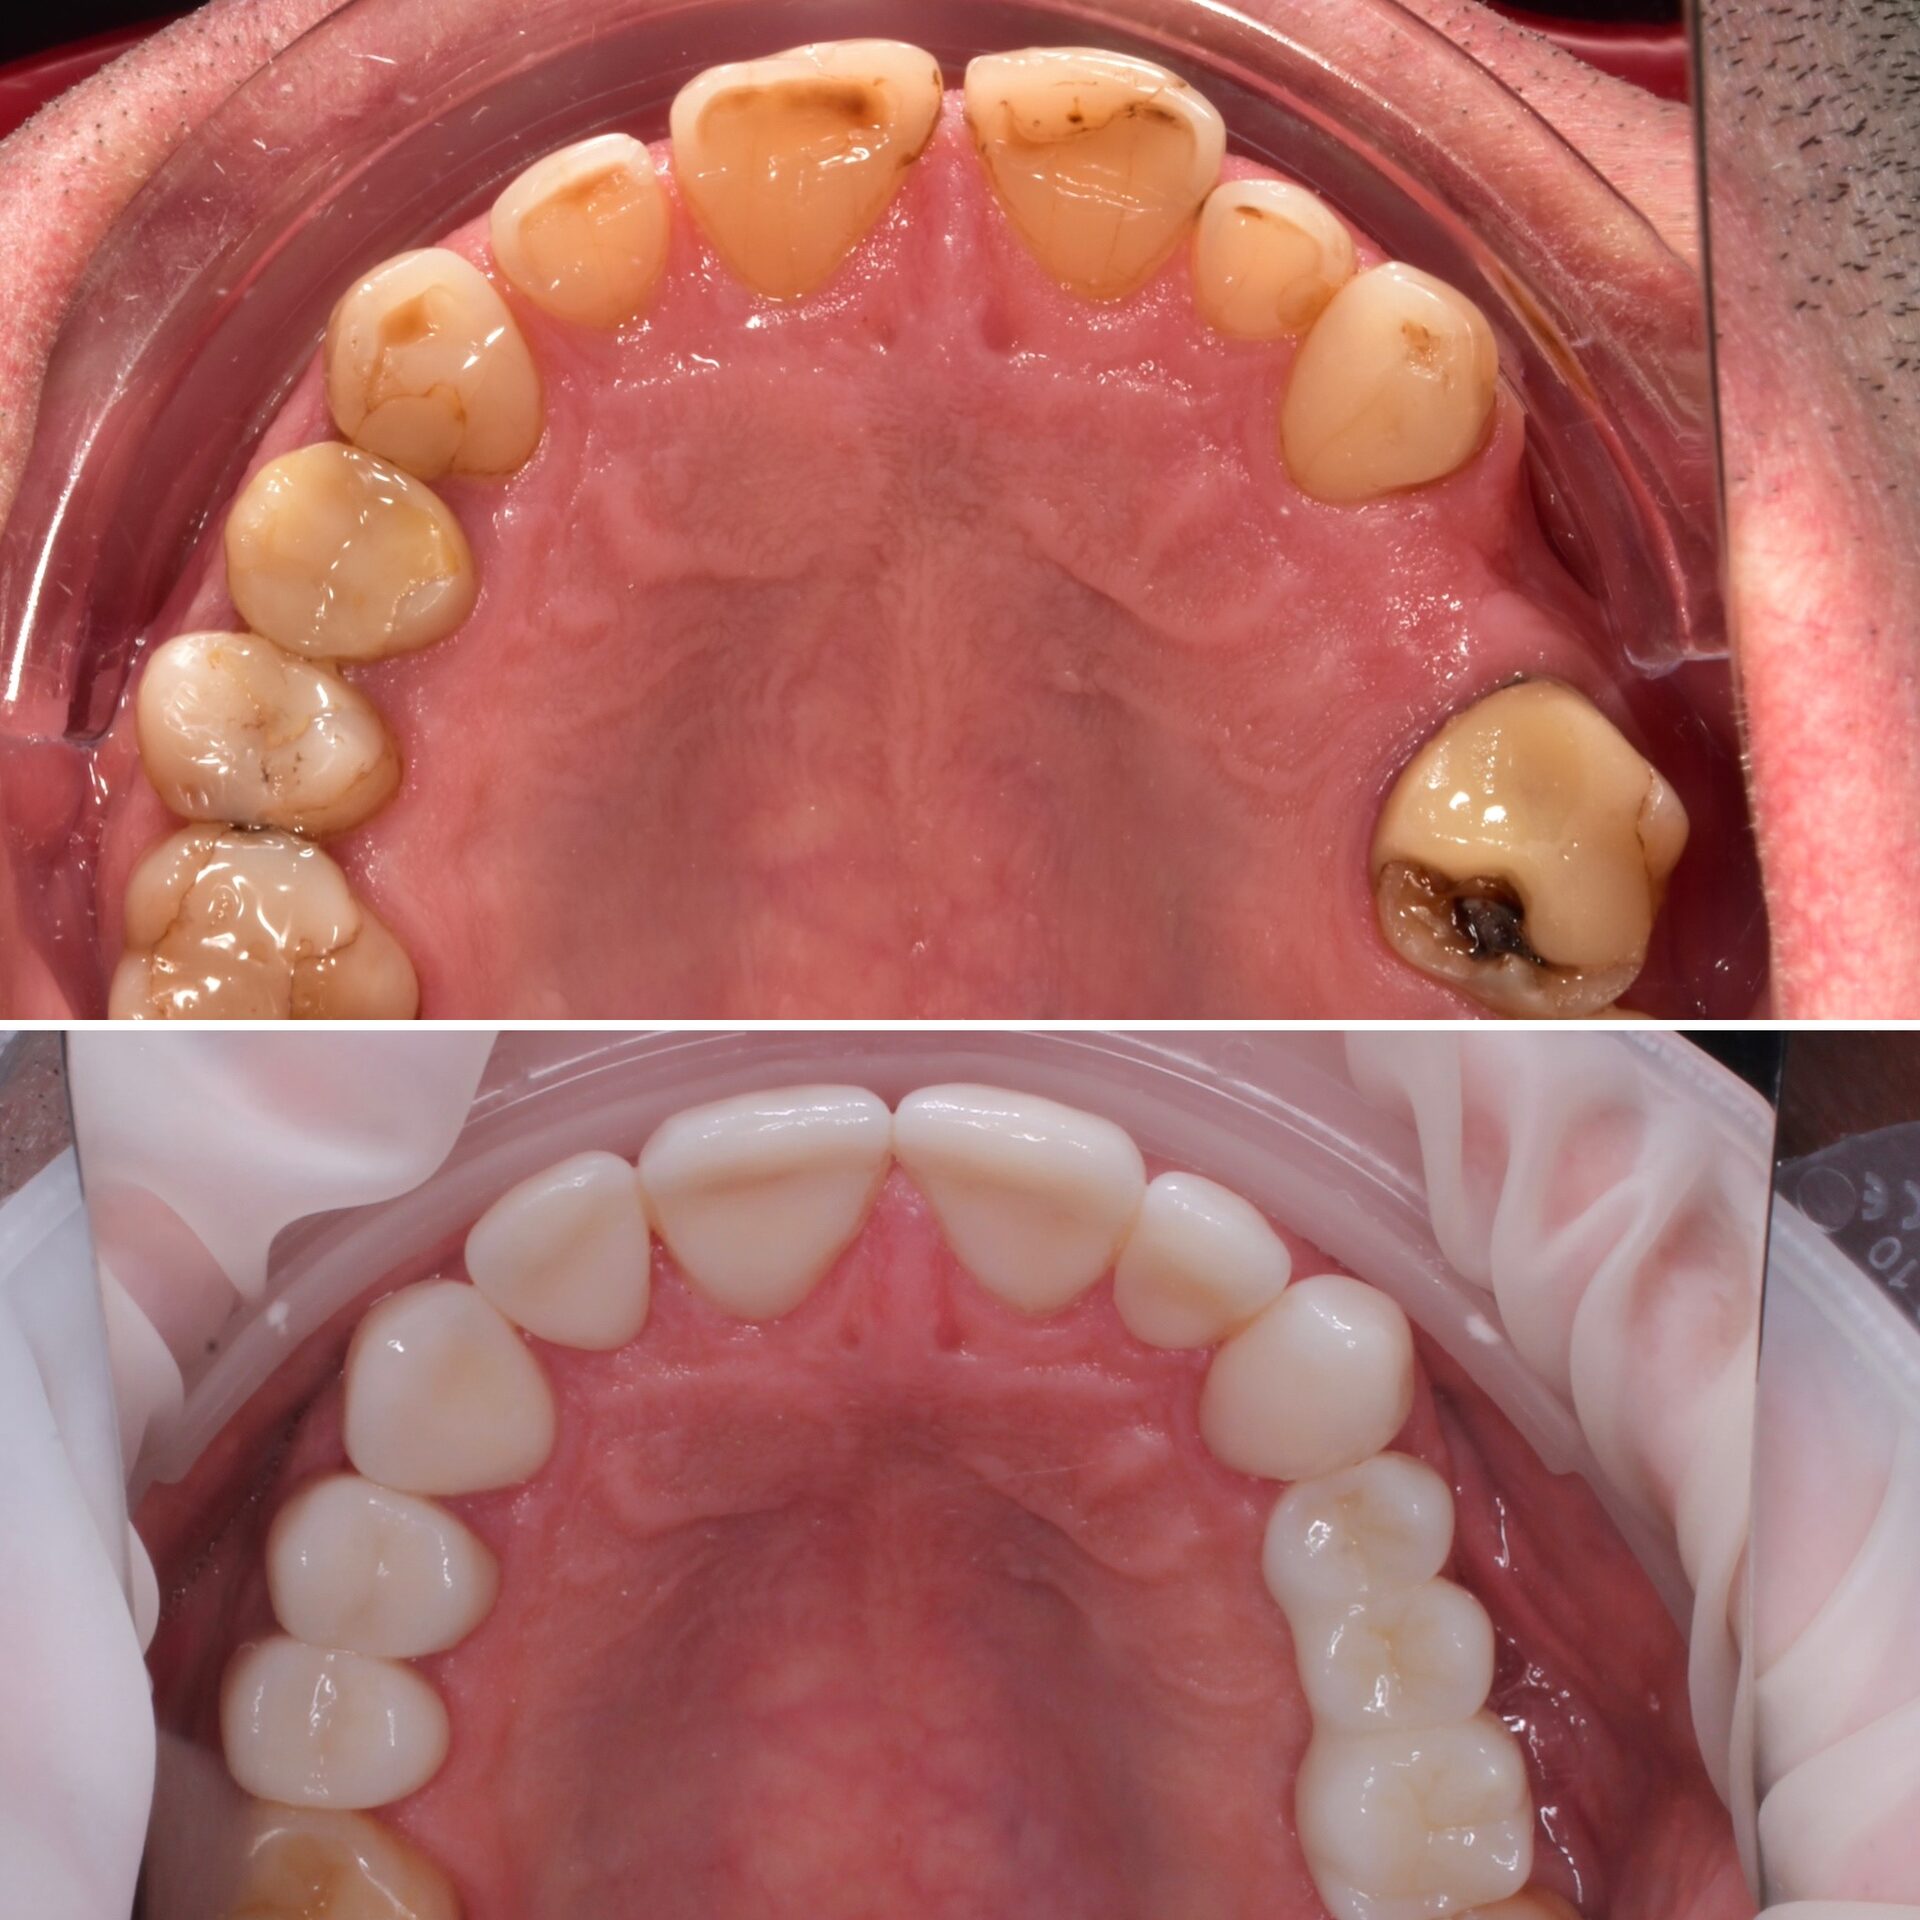

Лечение кариеса под микроскопом